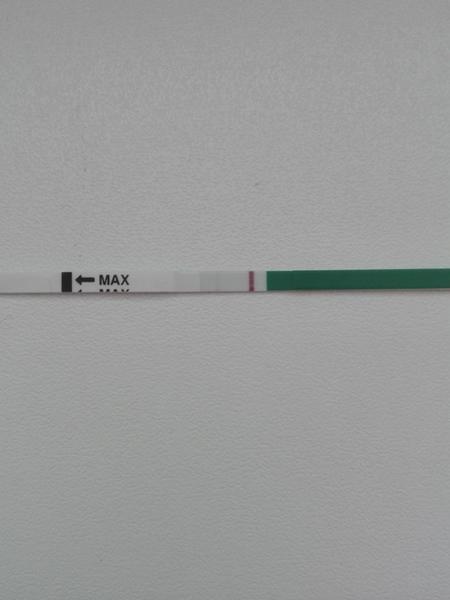

Duch na teste

ahojte babule, mam taku otazku...mate skusenost ze pocas 3 dni vam nesilnela druha ciarka na teste ale bola rovnaka???ako duch????